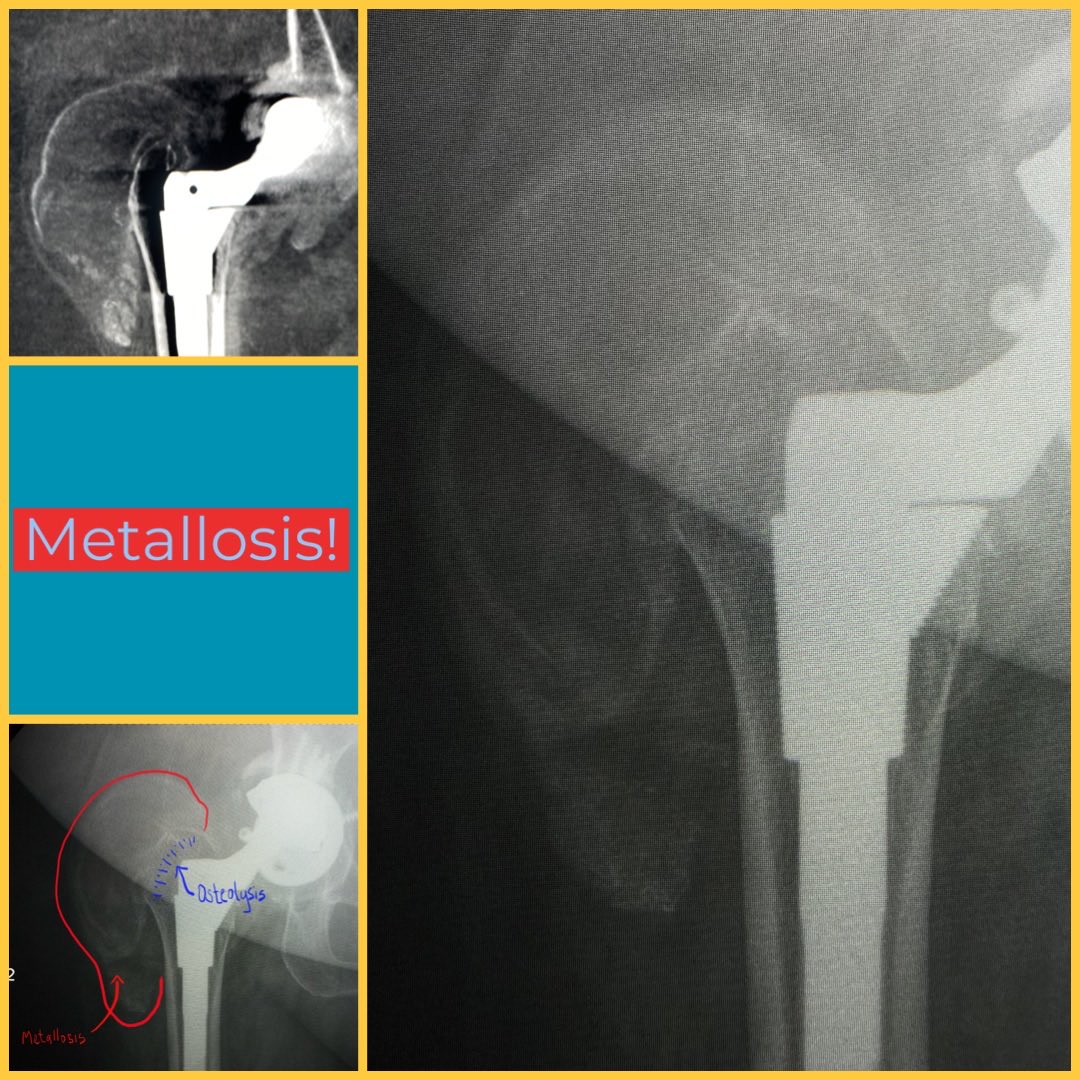

#radres education - Metallosis, also known as pseudotumor and usually co-existing with particle disease (osteolysis).pic.twitter.com/kq5bnAxFYs